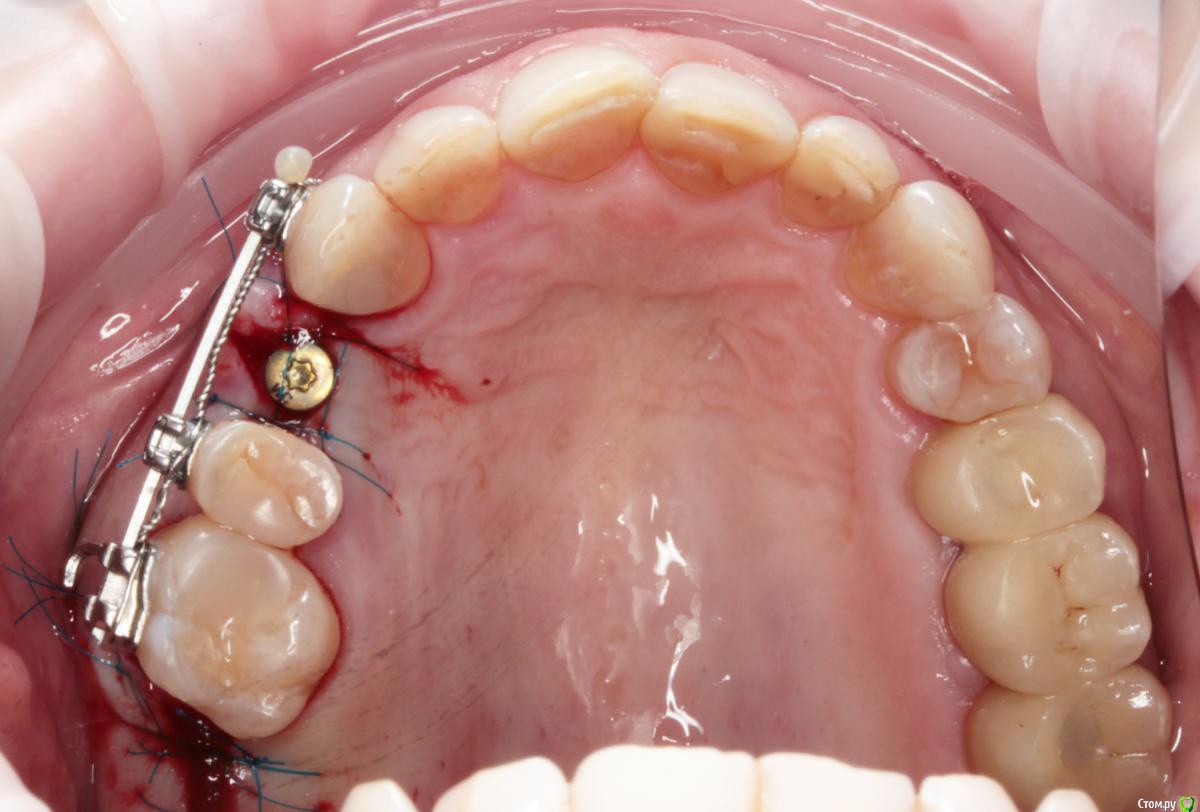

1) имплантация в позиции 15,17 з с закрытым синусом и незначительной НКР

2) коррекция слизистой в области 1-го сегм

3) имплантация с ССТ в позиции 24 з ( после дистализации 25,26 з), в области 27 з на момент  операции был гнойный синусит, отложили